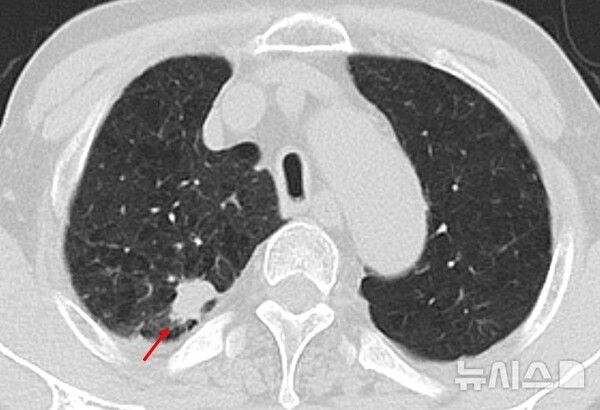

사진 = 뉴시스

국가 건강 검진에서 75세 이상의 고령자는 효율성 문제로 폐암 검진 대상에서 제외되는 경우가 많다. 그러나 최근 국내 연구팀이 70세 이상 고령자도 단 한 번의 저선량 CT(전산화단층촬영) 검진으로 폐암을 조기에 발견할 수 있음을 확인했다.

뉴시스 보도에 따르면, 장승훈 한림대학교성심병원 호흡기내과 교수, 강혜린 한림대학교동탄성심병원 호흡기내과 교수, 이춘택 분당서울대병원 호흡기내과 교수 연구팀은 '70세 이상 남성의 1회 저선량 CT 검진을 통한 폐결절 및 폐암 검출' 연구에서 이 같은 사실을 확인했다고 20일 밝혔다.

연구팀은 2010년부터 2023년까지 70세 이상의 재향군인 남성 1409명을 대상으로 저선량 흉부 CT 검사를 1회 시행하고 이후 3.6년간(참여자의 절반이 해당 기간 이상 추적) 추적관찰을 진행했다. 이를 통해 폐결절 및 폐암 유무, 폐암의 병기와 조직학적 분류(아형), 치료 방식 등을 분석했다. 검진 대상자의 평균 연령은 74.2세였고, 93%는 현재 흡연자이거나 과거 흡연경험이 있었다.

분석 결과 전체 대상자의 절반 이상인 55.8%(786명)에게서 폐결절이 발견됐고, 이 중 12.7%(179명)는 양성 폐결절이었다. 양성 폐결절은 암(악성)이 아니지만 극히 일부는 폐암으로 진단되거나 크기가 증가하며 폐암으로 진행될 수 있어 추적관찰이 요구된다. 양성 폐결절 환자에게 적절한 추적관찰을 진행한 결과 2.2%(31명)가 폐암으로 진단됐다.

저선량 흉부 CT 검사 후 폐암 진단까지 걸린 기간은 평균 9.3개월로 1년이 채 안 걸렸다. 이는 고령층에서 발견된 폐암이 더 공격적이고 빠르게 진행될 수 있음을 의미했다. 또 흡연 여부는 폐암 진단과 상관관계를 보였다. 현재 흡연자의 폐암 진단율은 3.6%(16명)로, 비흡연자 1.9%(2명)와 과거 흡연자 1.5%(13명)에 비해 높았다.

폐암 병기는 1기 48%(15명), 2기 13%(4명), 3기 16%(5명), 4기 23%(7명) 순이었다. 절반 이상(61%)이 폐암 초기 병기(1·2기)로 나타났으며, 이들은 비교적 조기에 암을 발견해 수술적 치료를 받을 수 있었다. 이외에도 폐암으로 진단된 전체 환자의 90%는 화학요법과 방사선치료 등 병기에 맞는 적절한 치료를 받았다.

강혜린 교수는 "이번 연구를 통해 고령자를 대상으로 한 번의 저선량 흉부 CT 검사만으로도 폐암의 조기 발견과 적절한 치료를 가능케 하는 실질적인 효과를 거둘 수 있음을 확인했다"며 "현재 폐암 국가검진 연령이 74세 이하로 제한돼 있지만 75세 이상에서도 폐암의 조기 발견과 적극적인 치료가 충분히 가능함을 시사한다"고 설명했다.

장승훈 교수는 "저선량 흉부 CT 검사는 특히 흡연력, 만성폐쇄성폐질환(COPD), 폐기종 등 폐암 고위험 인자를 가진 고령 환자에게 매우 유용한 도구가 될 수 있다"며 "이번 연구는 향후 폐암 검진정책 개선과 고령층의 폐암 사망률 감소에 기여할 것으로 기대된다"고 말했다.